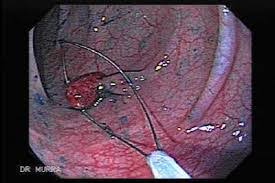

Polyp av sigmoid kolon som avslørt ved koloskopi. Visse matvarer kan redusere omfanget av polypper i tarmen, et forstadium til ondartede svulster. Polypper i tarmen er ikke kræft, men kan udvikle sig til kræft, hvis ikke de bliver fjernet. Polypper og adenomer (godartede små svulster) i tarmen, og som ikke blir behandlet. De er vanligvis godartede, men har risiko for kreftutvikling og skal derfor alltid fjernes. Men veldig få polypper vil bli kreft, og det tar mange år før dette skjer. Polypper kan behandles og er i de fleste tilfeller fullstendig godartede. Polypper i tarmen er vanligvis lokalisert i tykktarmen (kolon), eller endetarmen (rektum).

Polypper I Tarmen: Polyp av sigmoid kolon som avslørt ved koloskopi.